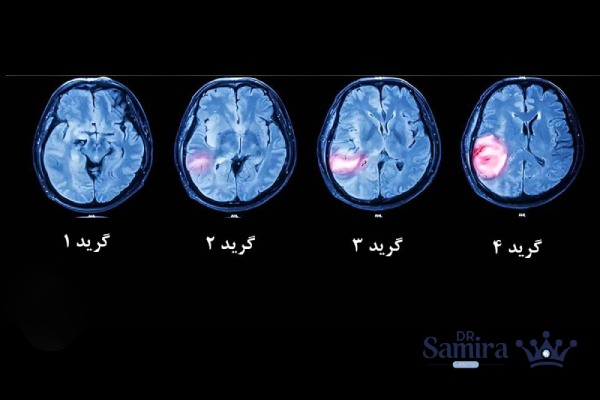

الیگودندروگلیوم گرید ۲ نوعی تومور مغزی است که از سلول هایی به نام الیگودندروسیت ها یا سلول های پشتیبان اعصاب منشاء میگیرد. این تومور در دستهی تومورهای اولیه مغز قرار دارد و رشد آهستهای دارد، اما در برخی موارد ممکن است با گذشت زمان به نوع تهاجمی یعنی گرید ۳ تبدیل شود. طبق طبقه بندی سازمان جهانی بهداشت (WHO)، برای تشخیص دقیق این نوع تومور باید دو ویژگی ژنتیکی در آن وجود داشته باشد: جهش در ژن IDH و حذف بخش هایی از کروموزوم های ۱ و ۱۹ (که به آن ۱p/۱۹q-codeletion گفته میشود). وجود این دو ویژگی، تشخیص الیگودندروگلیوم را قطعی میکند و آن را از سایر تومورهای گلیومی مانند آستروسیتوما متمایز میسازد.

تشخیص الیگودندروگلیوم گرید ۲ اصولا با ترکیب یافتههای تصویربرداری، بررسیهای بافت شناسی و تستهای ژنتیکی انجام میشود. اولین گام تصویربرداری با MRI مغز است که در آن تودهای با مرزهای نسبتا نامشخص در ناحیه سفید مغز دیده میشود. این تومور به آرامی رشد میکند و در MRI افزایش سیگنال در توالی های T2 و FLAIR مشاهده میشود. در برخی موارد، ماده حاجب درون تومور تجمع مییابد، اما برخلاف تومورهای بدخیم، این افزایش روشنایی خفیف است.